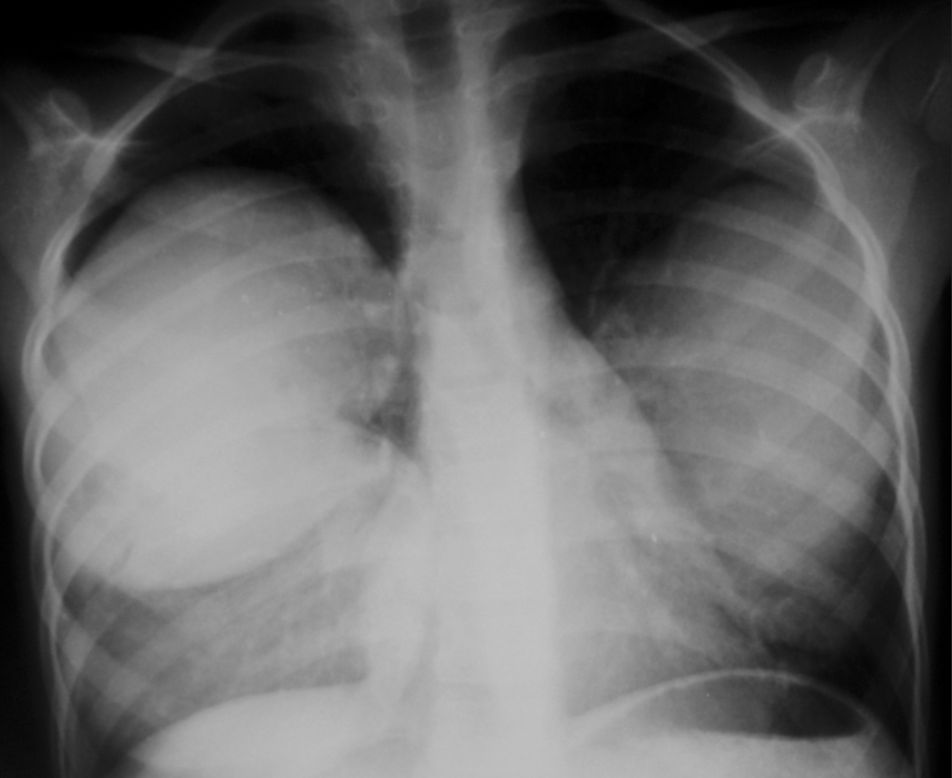

Chest Pain and Dyspnea in 9-year-old Boy Post category:Spot Diagnosis Post published:September 13, 2023 Share on Facebook Share on X (Twitter) Share on Pinterest Share on Email Share on Reddit Chest pain and dyspnea in 9-year-old boy A 9-year-old boy presented with chest pain and dyspnea. What could be the diagnosis ? FULL CASE AND ANSWER Share on Facebook Share on X (Twitter) Share on Pinterest Share on Email Share on Reddit Read more articles Previous PostDyschromic Patches, Plaques, and Poikiloderma on Upper Back Next PostPainless, Pruritic Papules and Verrucous Lesions You Might Also Like Varices of the Chest and Abdominal Wall November 9, 2021 Patient with Decreased Appetite, Vomiting, Weight Loss and a Mass Through the Umbilicus November 29, 2021 23-year-old Man Involved in a Motor Vehicle Accident April 19, 2022